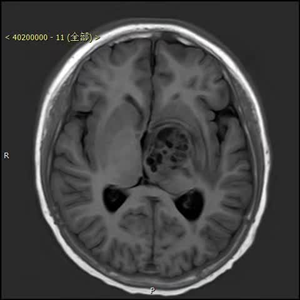

患者术后资料(下图)